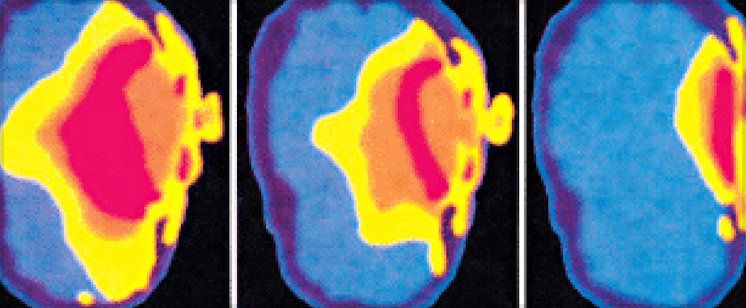

A new report published this week in American Journal of Epidemiology confirms that Canadians who have used cellphones for 558 hours or more have more than a doubled risk of brain cancer.

These important findings strengthen the association between cell phone use and glioma, which is an aggressive brain cancer.